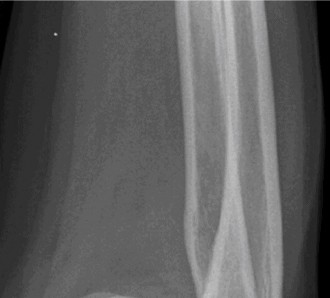

Understand the operative treatment of SC joint osteoarthritis and the important structures to preserve? CASE 29 Dr. Robert J. Stewart A 57-year-old, right-hand-dominant female presents with left shoulder pain and stiffness for the last 3 months. She has a history of diabetes, hypothyroidism, and breast cancer. She reports having difficulty sleeping on her left side. She localizes her pain over the deltoid insertion. The stiffness has become worse. The pain has been improving over the last 3 weeks but is exacerbated by extreme left shoulder motion. She is having difficulty dressing and combing her hair. She works as a statistical analyst and sits at a desk most of the day. On physical examination, she has normal strength with left shoulder abduction and external rotation, a negative cross-body adduction test, and no pain with a supinated O’Brien’s test. An x-ray is obtained and shown in Figure 2–76.

Figure 2–76

Of the following, what is the most likely diagnosis of this patient?

- Rotator cuff tear

- Calcific tendinitis

- Acromioclavicular joint arthritis

- Adhesive capsulitis

- Glenohumeral joint arthritis

The correct answer is (D). Adhesive capsulitis (AC) is a specific pathologic entity that produces subsynovial chronic inflammation resulting in capsular thickening, fibrosis, and adherence of the capsule to itself and the anatomic neck of the humerus. The thickened and stiff capsule causes pain and a restraint to motion. This is called primary, or idiopathic, AC. The remaining answer choices are incorrect and can result in symptoms similar to those of AC (i.e., loss of shoulder motion and pain), but their underlying etiology is different. It is important to recognize that all these conditions can cause a stiff and painful shoulder (a “frozen shoulder”) but is not necessarily AC. AC occurs more frequently in sedentary females in the non-dominant hand, and has been associated with diabetes mellitus, thyroid dysfunction, breast cancer treatment, cardiovascular disease and cerebrovascular disease.

The patient is diagnosed with stage 3 adhesive capsulitis. On physical

examination, which of the following is the most likely to be found?

- Decreased passive and active range of motion of the shoulder in all planes

- Decreased passive and active range of motion of the shoulder in external rotation

- Pain with passive and active range of motion of the shoulder

- Pain with resisted forward flexion of the arm

- Pain with external rotation of the arm